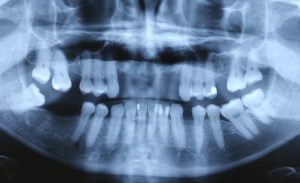

Paciente procurou a área de CBMF da Unicamp com a pré-maxila edêntula (Figuras 1 e 2) e foi submetido à técnica Screw Tent Poleutilizando os parafusos da linha Orth – Implacil de Bortolli (Figura 3). Do lado esquerdo da pré-maxila foram instalados três parafusos que apresentavam roscas em toda superfície, enquanto que do lado direito foram instalados três parafusos que não apresentam roscas no terço cervical (Figuras 4 e 5). Biomaterial associado com PRF (Stick Bone) foi adequadamente acomodado na região entre os parafusos e recoberto por membranas de PRF (Figuras 6 e 7). Uma sutura livre de tensão foi realizada para finalizar o procedimento cirúrgico (Figura 8).

figuras 1 e 2